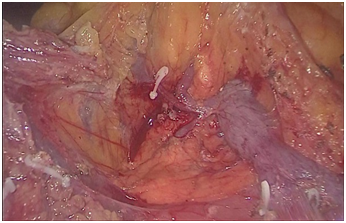

腹腔镜术中照片